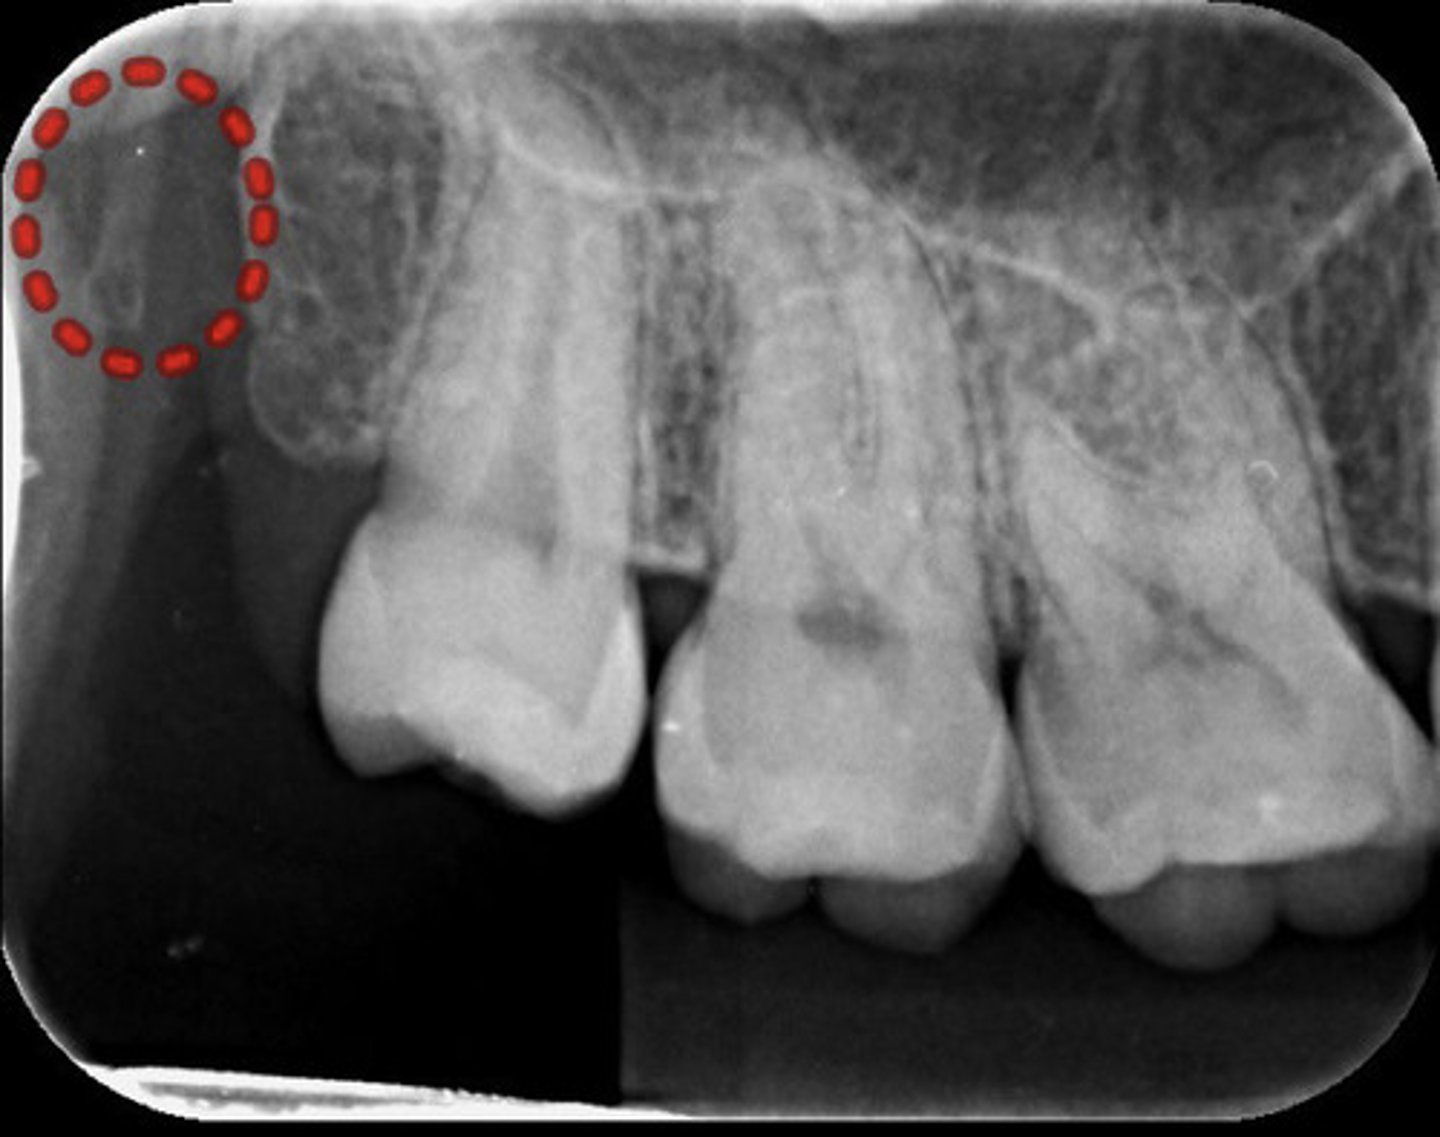

What is the red dotted line circling?

Maxillary sinus